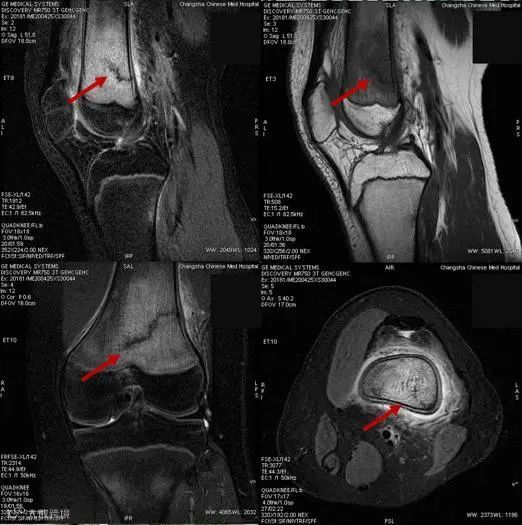

在行膝关节磁共振成像检查时,医生发现,罗同学的右侧股骨下段骨折并广泛骨髓水肿 ,被诊断为应力性骨折。